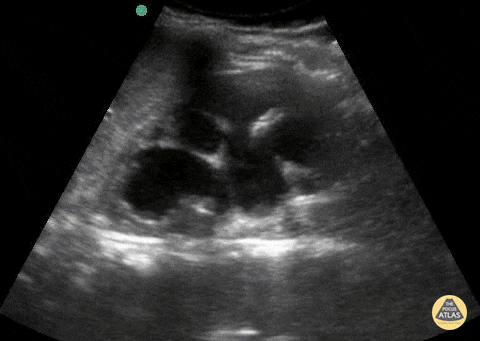

Renal & Bladder Pathology

Peds-Genitourinary